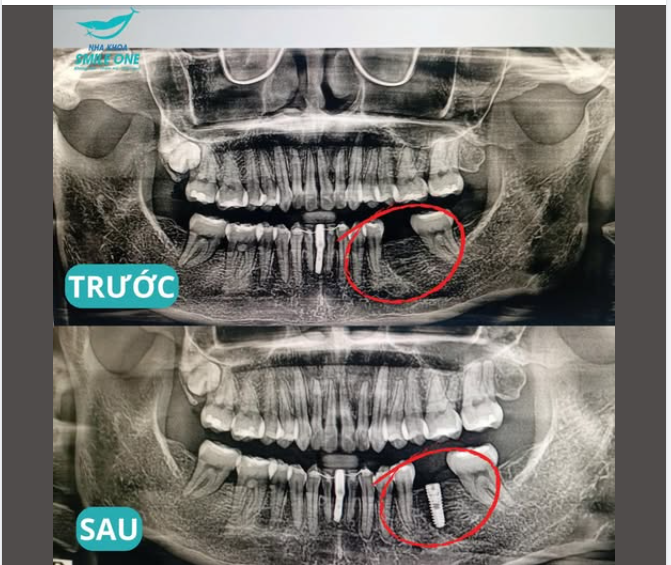

BAO LÂU SAU KHI MẤT RĂNG THÌ BẮT ĐẦU TIÊU XƯƠNG HÀM

Sau khi mất răng, xương hàm tại vị trí đó không còn được kích thích bởi lực ăn nhai và bắt đầu tiêu dần theo thời gian. Xem thêm trồng răng implant

Việc trì hoãn phục hồi răng có thể khiến quá trình điều trị sau này trở nên phức tạp hơn.